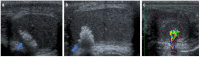

Pre- and post-pubertal testicular tumors are two distinct entities in terms of epidemiology, diagnosis and treatment. Most pre-pubertal tumors are benign; the most frequent are teratomas, and the most common malignant tumors are yolk-sac tumors. Post-pubertal tumors are similar to those found in adults and are more likely to be malignant. Imaging plays a pivotal role in the diagnosis, staging and follow-up. The appearance on ultrasonography (US) is especially helpful to differentiate benign lesions that could be candidates for testis-sparing surgery from malignant ones that require radical orchidectomy. Some specific imaging patterns are described for benign lesions: epidermoid cysts, mature cystic teratomas and Leydig-cell tumors. Benign tumors tend to be well-circumscribed, with decreased Doppler flow on US, but malignancy should be suspected when US shows an inhomogeneous, not-well-described lesion with internal blood flow. Imaging features should always be interpreted in combination with clinical and biological data including serum levels of tumor markers and even intra-operative frozen sections in case of conservative surgery to raise any concerns of malignity. This review provides an overview of imaging features of the most frequent testicular and para-testicular tumor types in children and the value of imaging in disease staging and monitoring children with testicular tumors or risk factors for testicular tumors.